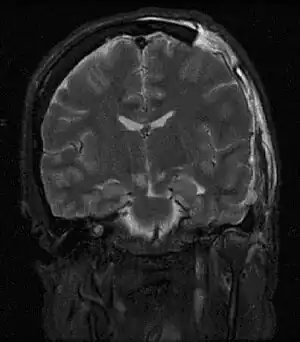

| Severely high ICP can cause the brain to herniate. | |

One of the most damaging aspects of brain trauma and other conditions, directly correlated with poor outcome, is an elevated intracranial pressure.[9] ICP is very likely to cause severe harm if it rises too high.[10] Very high intracranial pressures are usually fatal if prolonged, but children can tolerate higher pressures for longer periods.[11] An increase in pressure, most commonly due to head injury leading to intracranial hematoma or cerebral edema, can crush brain tissue, shift brain structures, contribute to hydrocephalus, cause brain herniation, and restrict blood supply to the brain.[12] It is a cause of reflex bradycardia.[13]

Severely raised ICP, if caused by a unilateral space-occupying lesion (e.g. a hematoma) can result in midline shift, a dangerous sequela in which the brain moves toward one side as the result of massive swelling in a cerebral hemisphere. Midline shift can compress the ventricles and lead to hydrocephalus.[16]